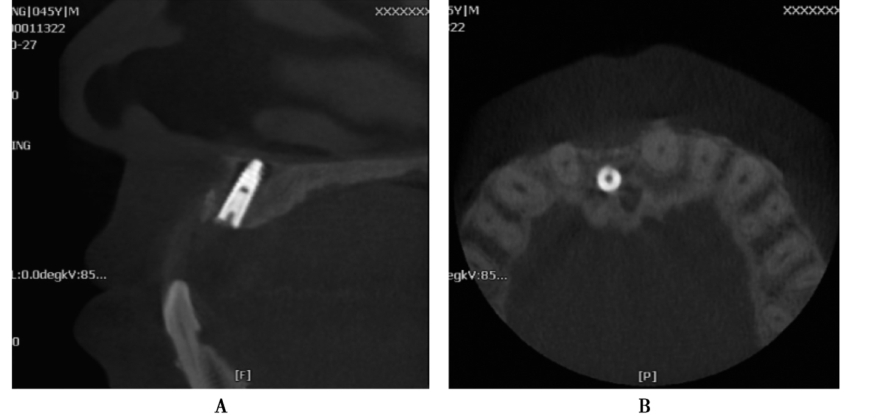

图7 术前矢状位

CBCT片显示牙槽骨密度低,正在愈合中

图8 术后CBCT片矢状位

显示种植体植入5个月后2期修复前的状况

图9 术前术后矢状位CBCT片

A.牙槽骨密度及高度长度均好;B.显示种植体植入后的位置及高度良好